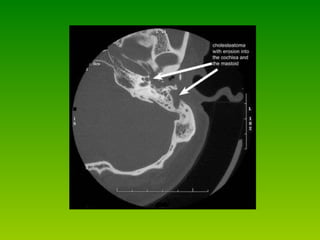

Radiological assessment * Plain radiogram  : it is of value in cholesteat  -omatus cases(shows lytic lesions) ,also it detect variation in anatomic landmarks. * CT-Scan :   CTscanning  performed when:  1. intratemporal or intracranial  complications are suspected  2. surgical intervention being planned 3.to study anatomy of temporal bone These studies should include both axial & coronal fine cuts (1-1.5mm) through the temporal bone.

Evaluation - Audiology  – usually conductive loss. - Imaging   * CT temporal bone   :  for  -revision cases  -complications of chronic suppurative otitis media  -sensorineural hearing loss  -vestibular symptom  -other complications of cholesteatoma

Radiological assessment *Plain radiogram : it is of value in cholesteat -omatus cases(shows lytic lesions) ,also it detect variation in anatomic landmarks. * CT-Scan : CTscanning performed when: 1. intratemporal or intracranial complications are suspected 2. surgical intervention being planned 3.to study anatomy of temporal bone These studies should include both axial & coronal fine cuts (1-1.5mm) through the temporal bone.